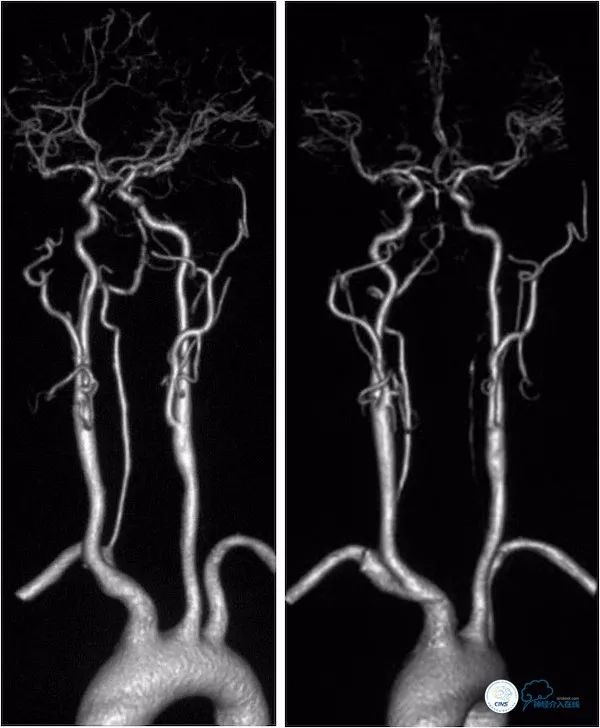

头颈部CTA:左椎动脉闭塞,右椎动脉V4段狭窄,基底动脉局限性狭窄,双侧后交通动脉开放(图4)。

图4

DSA:双侧颈动脉系统未见异常,双侧后交通动脉开放,右颈动脉造影可见基底动脉中上段显影。左椎动脉闭塞,右椎动脉V4段重度狭窄,基底动脉中段偏心重度狭窄(图5-8)。